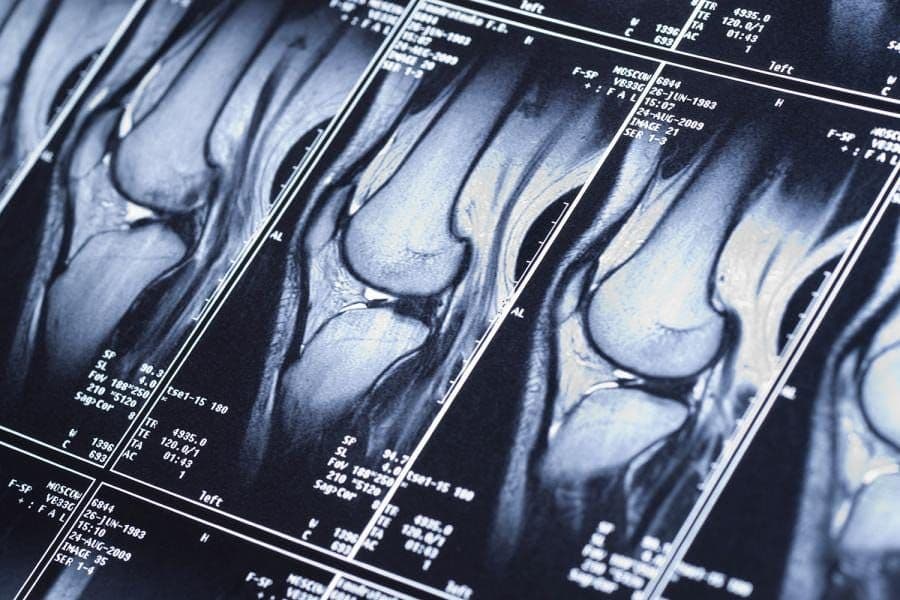

In 2019, Facebook AI Research (FAIR) and NYU Langone Health hosted the inaugural fastMRI Challenge↗ to make MRI scans up to 10X faster with AI. As part of the competition, NYU Langone Health released fully anonymized raw data and image datasets of 17K+ MRIs↗ to accelerate the clinical adoption of ML in MRI research broader machine learning community.

The annual campus-wide fastMRI Challenge at Seoul National University (SNU) hosted by the College of Engineering in conjunction with AIRS Medical — a medical AI startup founded by the winners of the 2020 FAIR-NYU fastMRI Challenge — succeeds this initiative. Every year, the competition brings together over 150 teams from 30+ disciplines to explore the latest trends in ML-accelerated MRI imaging and build state-of-the-art reconstruction models with real-world clinical data and powerful GPU resources dedicated to the challenge.

MRI reconstruction is both a GPU- and data-intensive task. The winning model of the 2020 fastMRI Challenge by AIRS Medical, for example, had 200M+ parameters trained on 4 NVIDIA V100s for 7 days. SNU wanted to scale that 150X — an environment in which 150+ teams could each train and optimize their own models.